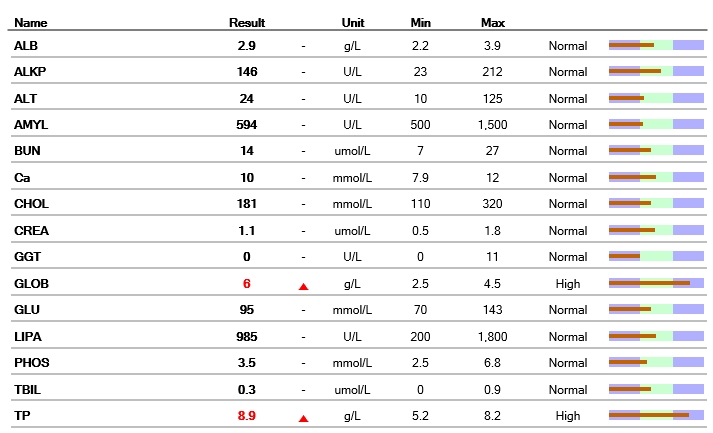

간의 값, 신장의 값 등을 평가하는 혈청 화학 검사의 결과입니다.